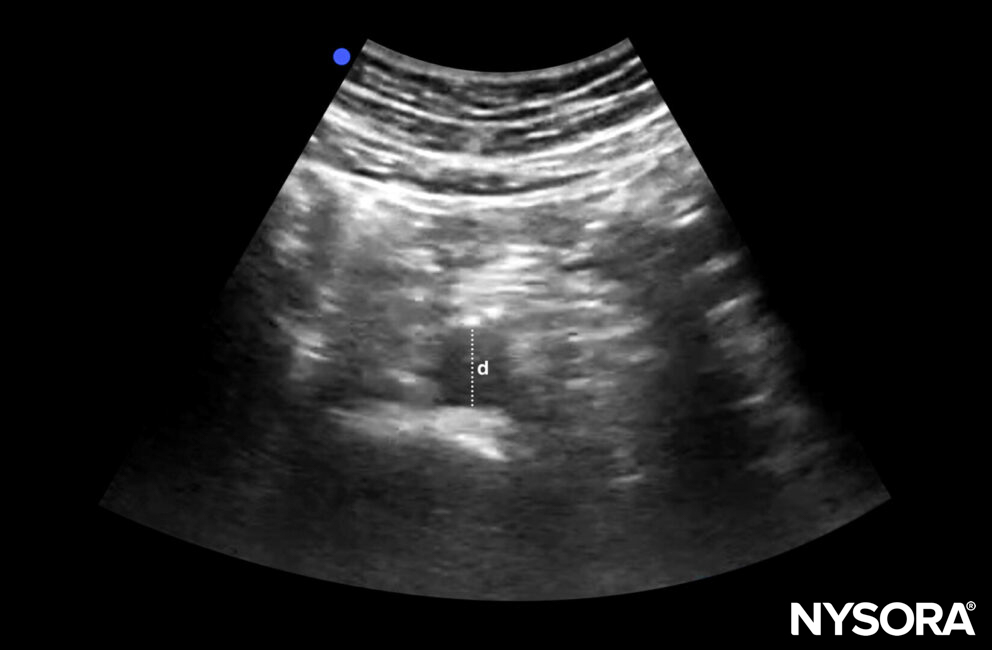

A normal abdominal aorta is 2 cm in diameter.

Diameter (d) of a normal abdominal aorta: 2 cm.